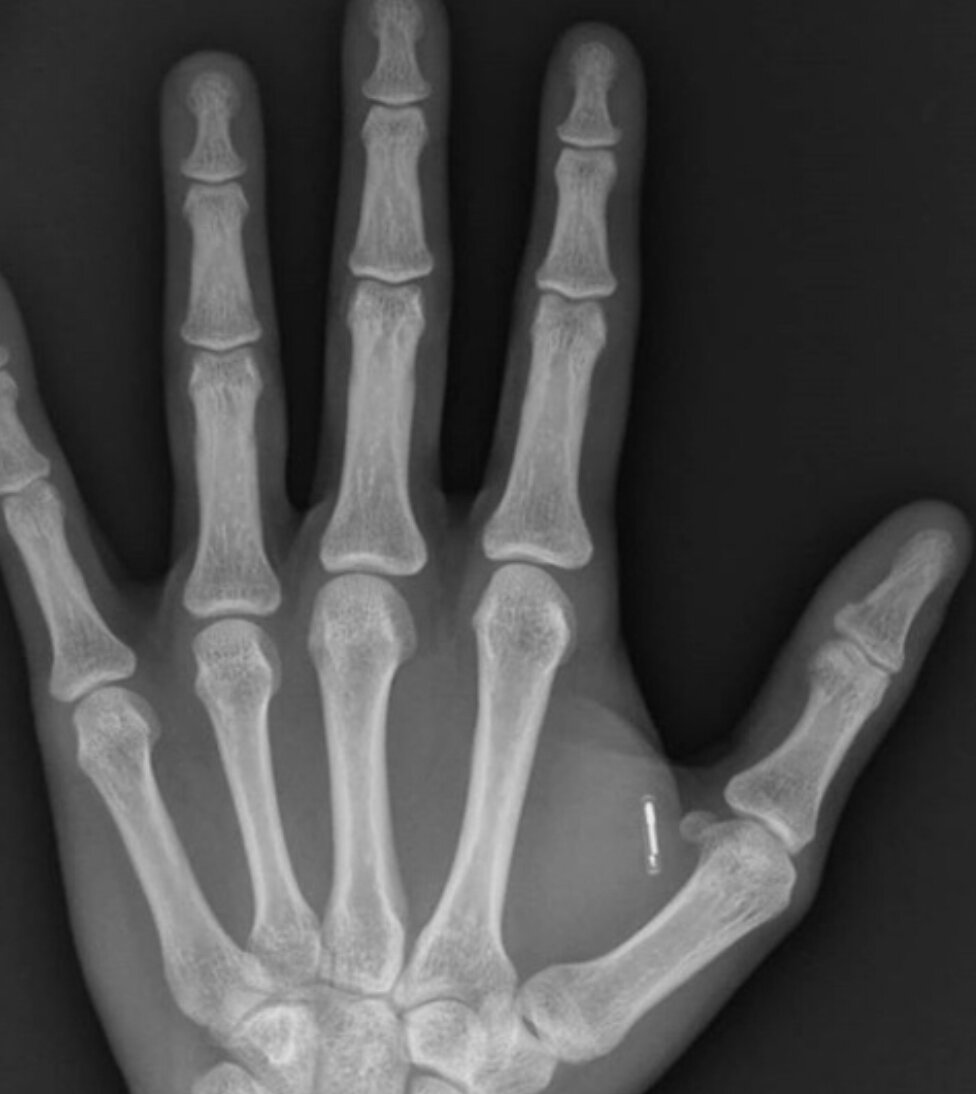

Массовое чипирование людей!